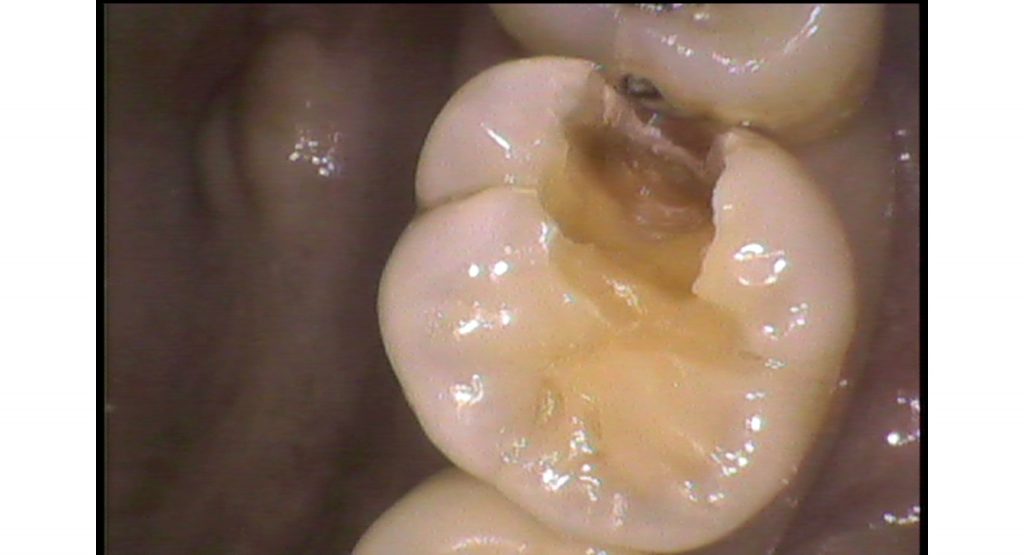

抜髄処置 Case1

虫歯菌(ミュータンス菌)によりエナメル質が溶け神経まで虫歯菌が進行すると神経が炎症を起こし痛みを伴います。症状としては、冷たい物や温かい物がしみる、何もしなくても痛いと感じることがあります(この症状があったからと言って必ず神経を取るわけではありません)。神経まで虫歯が進行しているにもかかわらず治療せずに放置すると、根の先に膿がたまり根の先の顎の骨が溶けることがあります。